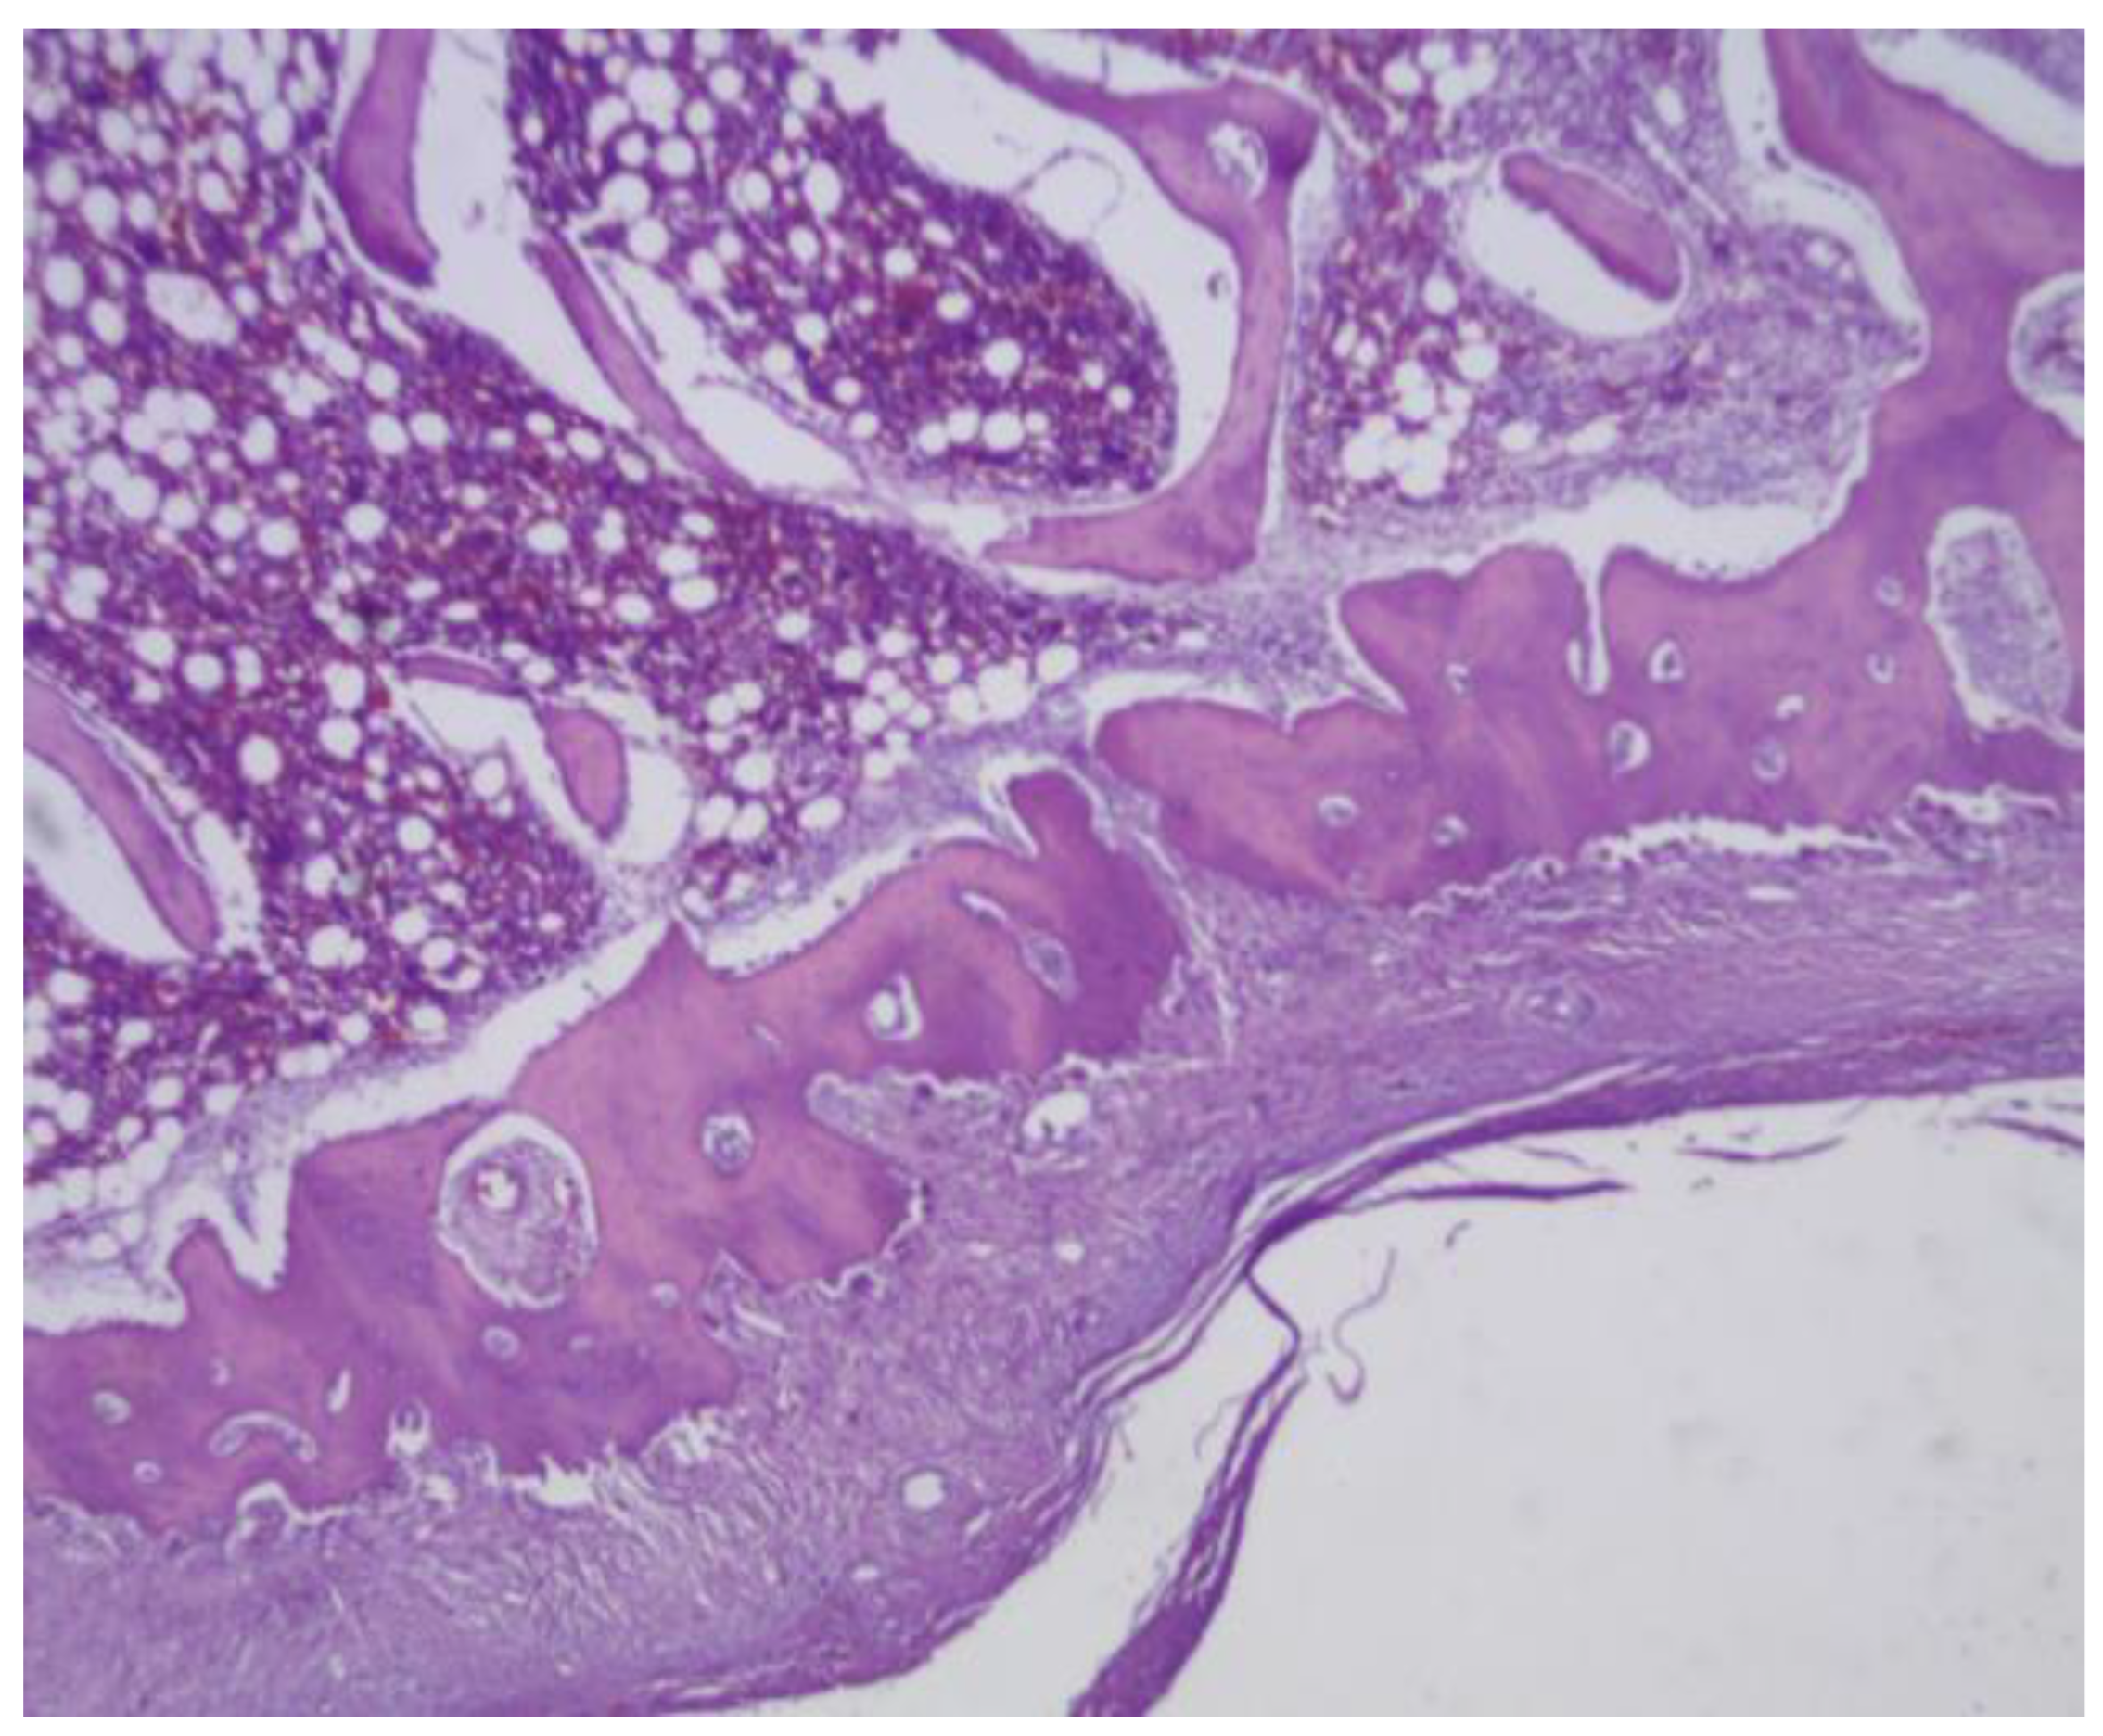

Figure 24. (A) PLA screw insertion site is in the articular cartilage. (B) presence of small-caliber blood vessels scattered throughout the tissue, along with signs of synovial metaplasia in the epithelium surrounding the screw.

PLA: The PLA screw insertion site is in the articular cartilage. At this early stage, no evidence of bone growth is observed. However, a notable epithelial change is present around the screw, suggesting the development of a pseudoarthrosis. The histological section also reveals the presence of small-caliber blood vessels scattered throughout the tissue, along with signs of synovial metaplasia in the epithelium surrounding the screw. Additionally, areas of hyaline cartilage are identified.(Figure 24)

Figure 26. PLDLLA periprosthetic fibrosis is mild, indicating a moderate tissue response without excessive fibrous encapsulation.

PLDLLA: In this case, histological analysis reveals absence of osseointegration, indicating that no direct union has been established between the PLDLLA implant and the surrounding bone tissue. However, fibrointegration is present, suggesting the presence of fibrous tissue at the bone-implant interface. Periprosthetic fibrosis is mild, indicating a moderate tissue response without excessive fibrous encapsulation. Neovascularization is high, reflecting significant formation of new blood vessels in the area adjacent to the implant. Focal osteoid presence is observed, indicating a limited degree of osteogenic activity at the implant interface. (Figure 26)

Figure 29. The presence of mature bone, indicates a favourable osteointegrative environment in PLDLLA screw.

PLDLLA: Sections revealed mature bone with minimal periprosthetic connective tissue, abundant neovascularisation, and a moderate inflammatory infiltrate. The lack of osteoid suggests that bone mineralisation occurred efficiently, without signs of delayed or abnormal matrix deposition. This, along with the presence of mature bone, indicates a more favourable osteointegrative environment compared to PEEK. The absence of synovial metaplasia reinforces the notion of a stable and well-regulated local tissue response, highlighting PLDLLA´s potential for successful integration and biofunctionality within bone tissue. (Figure 29)